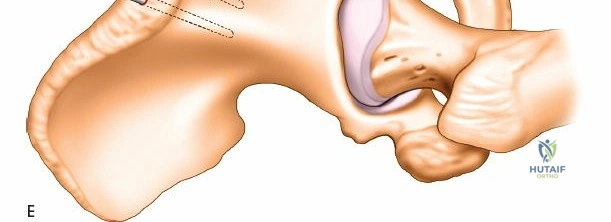

Topographic Anatomy and Safe Zones

Understanding the cross-sectional anatomy of the upper extremity is critical for safe pin placement.

Humerus Safe Zones

The humerus presents significant challenges due to the course of the radial nerve, axillary nerve, and brachial artery.

* Proximal Third: The safe zone is located laterally. Pins can be placed from lateral to medial, avoiding the axillary nerve, which runs transversely approximately 5 to 7 cm distal to the lateral acromion.

* Middle Third: This is the most hazardous region. The radial nerve spirals from posterior to anterior along the spiral groove. Anterolateral pin placement is generally safe if placed distal to the deltoid insertion, but open dissection to the periosteum is mandatory.

* Distal Third: The radial nerve pierces the lateral intermuscular septum to enter the anterior compartment. Pins are typically placed posteriorly or posterolaterally, directly through the triceps tendon or muscle belly, ensuring the radial nerve is protected anteriorly.